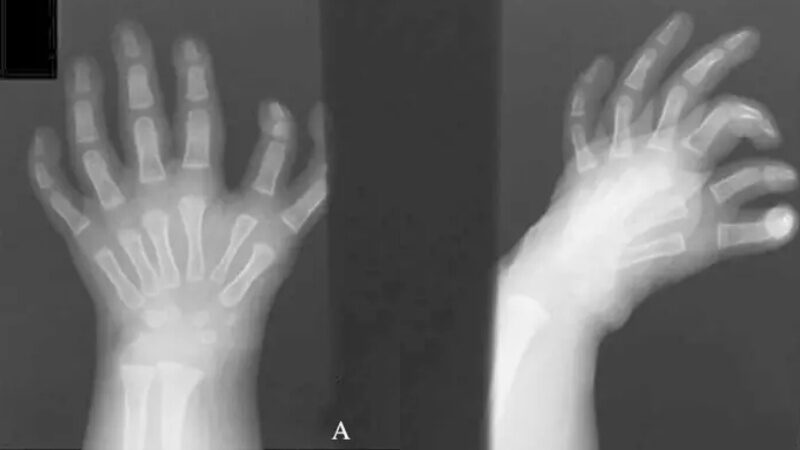

กระแสไวรัลในโลกออนไลน์กำลังฮือฮากับสภาวะทางการแพทย์หายากเรียกว่ามือกระจก (Mirror hand syndrome) ในทางการแพทย์เรียกว่า ulnar dimelia โดยเป็นความพิการแต่กำเนิดที่หายากมาก ซึ่งเกิดมาพร้อมกับนิ้ว 7-10 นิ้วในมือข้างเดียวหรือทั้งสองข้าง ในบางกรณีแขนและข้อศอกของคุณอาจได้รับผลกระทบ

ภาวะนี้จะแสดงนิ้วมือดูเหมือนภาพสะท้อนในกระจกจากจุดกึ่งกลางของมือมีสามนิ้ว ได้แก่ นิ้วกลาง นิ้วนาง และนิ้วก้อย โดยปกติผู้ที่มีภาวะโรคนี้จะไม่มีนิ้วหัวแม่มือ ทำให้นิ้ว แขน และมือเคลื่อนไหวได้จำกัด อาจนำไปสู่ปัญหาด้านความคล่องแคล่ว ซึ่งพบผู้ป่วยรายแรกในปี พ.ศ. 2395 ตั้งแต่นั้นมา มีรายงานผู้ป่วยน้อยกว่า 100 ราย

ภาพจาก AmericanRoentgenRaySociety

นอกจากลักษณะนิ้วหลายนิ้วและไม่มีนิ้วหัวแม่มือแล้ว ภาวะนี้อาจทำให้ข้อมืองอเล็กน้อยและงอข้อศอกได้ แต่ในบางกรณีข้อศอกอาจตรงและงอหรือหมุนได้ยาก อย่างไรก็ตาม มือกระจกก็สามารถรักษาได้ด้วยการผ่าตัด เพื่อแก้ไขลักษณะทางกายภาพและการทำงานของมือที่ได้รับผลกระทบ